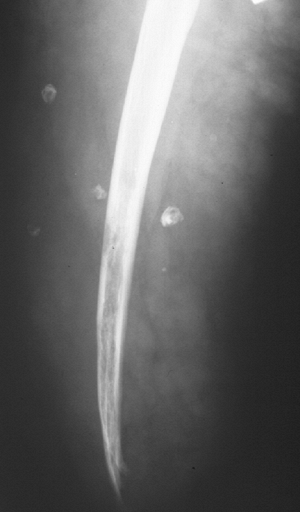

Deep lipomas (Fig. 11-1)

Fatty intramuscular shadow

Homogeneous fatty signal on all MRI sequences

No gadolinium enhancement

Occasional entrapped muscle fibers or fibrous strands

Figure 11-1 Inramuscular lipoma of the proximal forearm. (A) The fatty soft tissue shadow is shown within the muscle of the proximal forearm by plain radiograph. Axial T1-weighted (B) and T2-weighted (C) MR imaging studies show homogenous fatty signal characteristics identical to that of the subcutaneous fat.